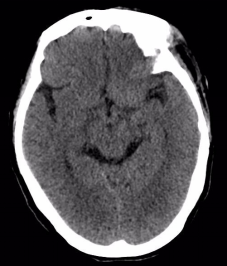

附女士,今年50岁,因车祸头部受伤,意识障碍4小时急诊入院。入院时,患者呈昏迷状,左侧瞳孔散大,头部、腕部、腹部等受伤10余处。急诊CT提示硬膜外血肿,中线移位明显,脑实质明显受压内移,左侧侧脑室受压变窄,病情凶险,手术指征明确。

“脑疝合并多发伤病人,需马上急诊手术!”朴金伟一边下医嘱,一边安排护士老师及联系手术室准备手术。护理团队仅仅耗时15分钟完成了剔头背皮、导尿、抽血、合血等一系列术前准备。

16时5分,神经外科张卫东主任、朴金伟团队急诊全麻下为患者行开颅血肿清除减压术,同时行彩超检查腹腔脏器。经胃肠小儿外科专家会诊后,考虑肠道损伤可能性大,暂时禁食、胃肠减压、抗感染、肠外营养支持、补液等治疗,待颅内手术后再行进一步检查和治疗。